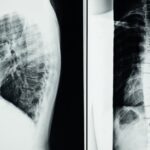

Une protrusion discale se produit lorsque le disque intervertébral se déplace légèrement sans se rompre, causant une pression sur les nerfs environnants. Cela peut entraîner des douleurs et une gêne significative. Reconnaître les symptômes est essentiel pour un diagnostic précoce et une rééducation efficace.

Consulter un professionnel de santé est fondamental pour évaluer la gravité de la protrusion discale et choisir la meilleure voie de traitement. Un diagnostic approfondi, potentiellement accompagné d’examens d’imagerie, permet de définir un plan de réhabilitation adapté. De plus, un suivi régulier assure que le patient reste sur la bonne voie pour sa guérison.

Une IRM ou une radiographie est souvent nécessaire pour confirmer le diagnostic d’une protrusion discale.